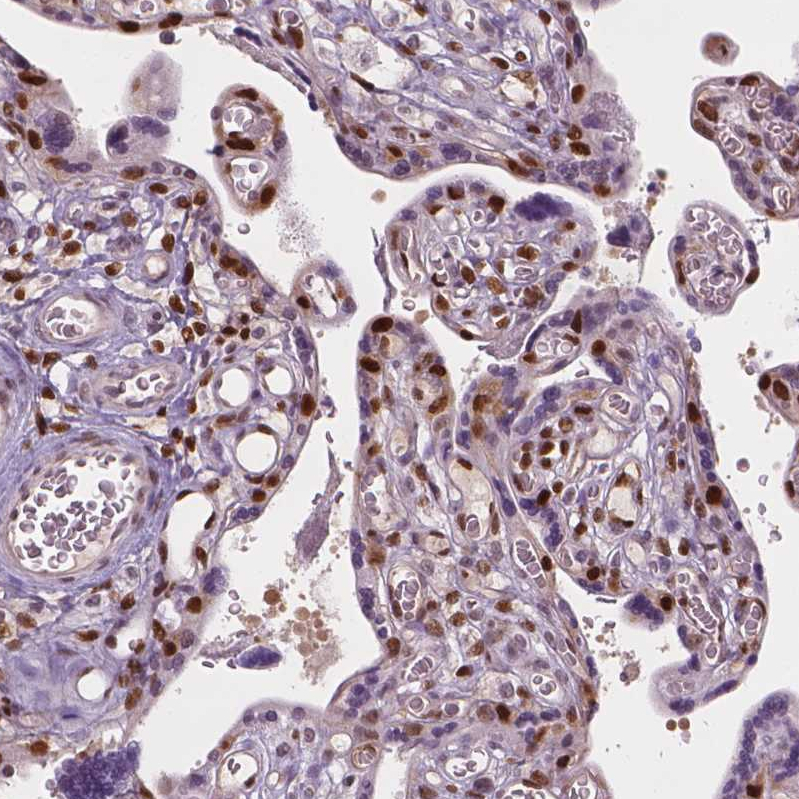

Immunohistochemistry analysis in human placenta and lymph node tissues using HPA002924 antibody. Corresponding CDKN1C RNA-seq data are presented for the same tissues.